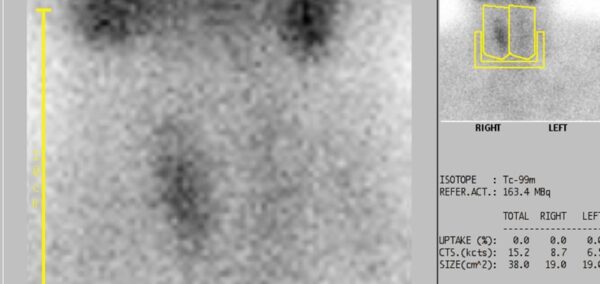

Thyroid scintigraphy

Scintigraphy